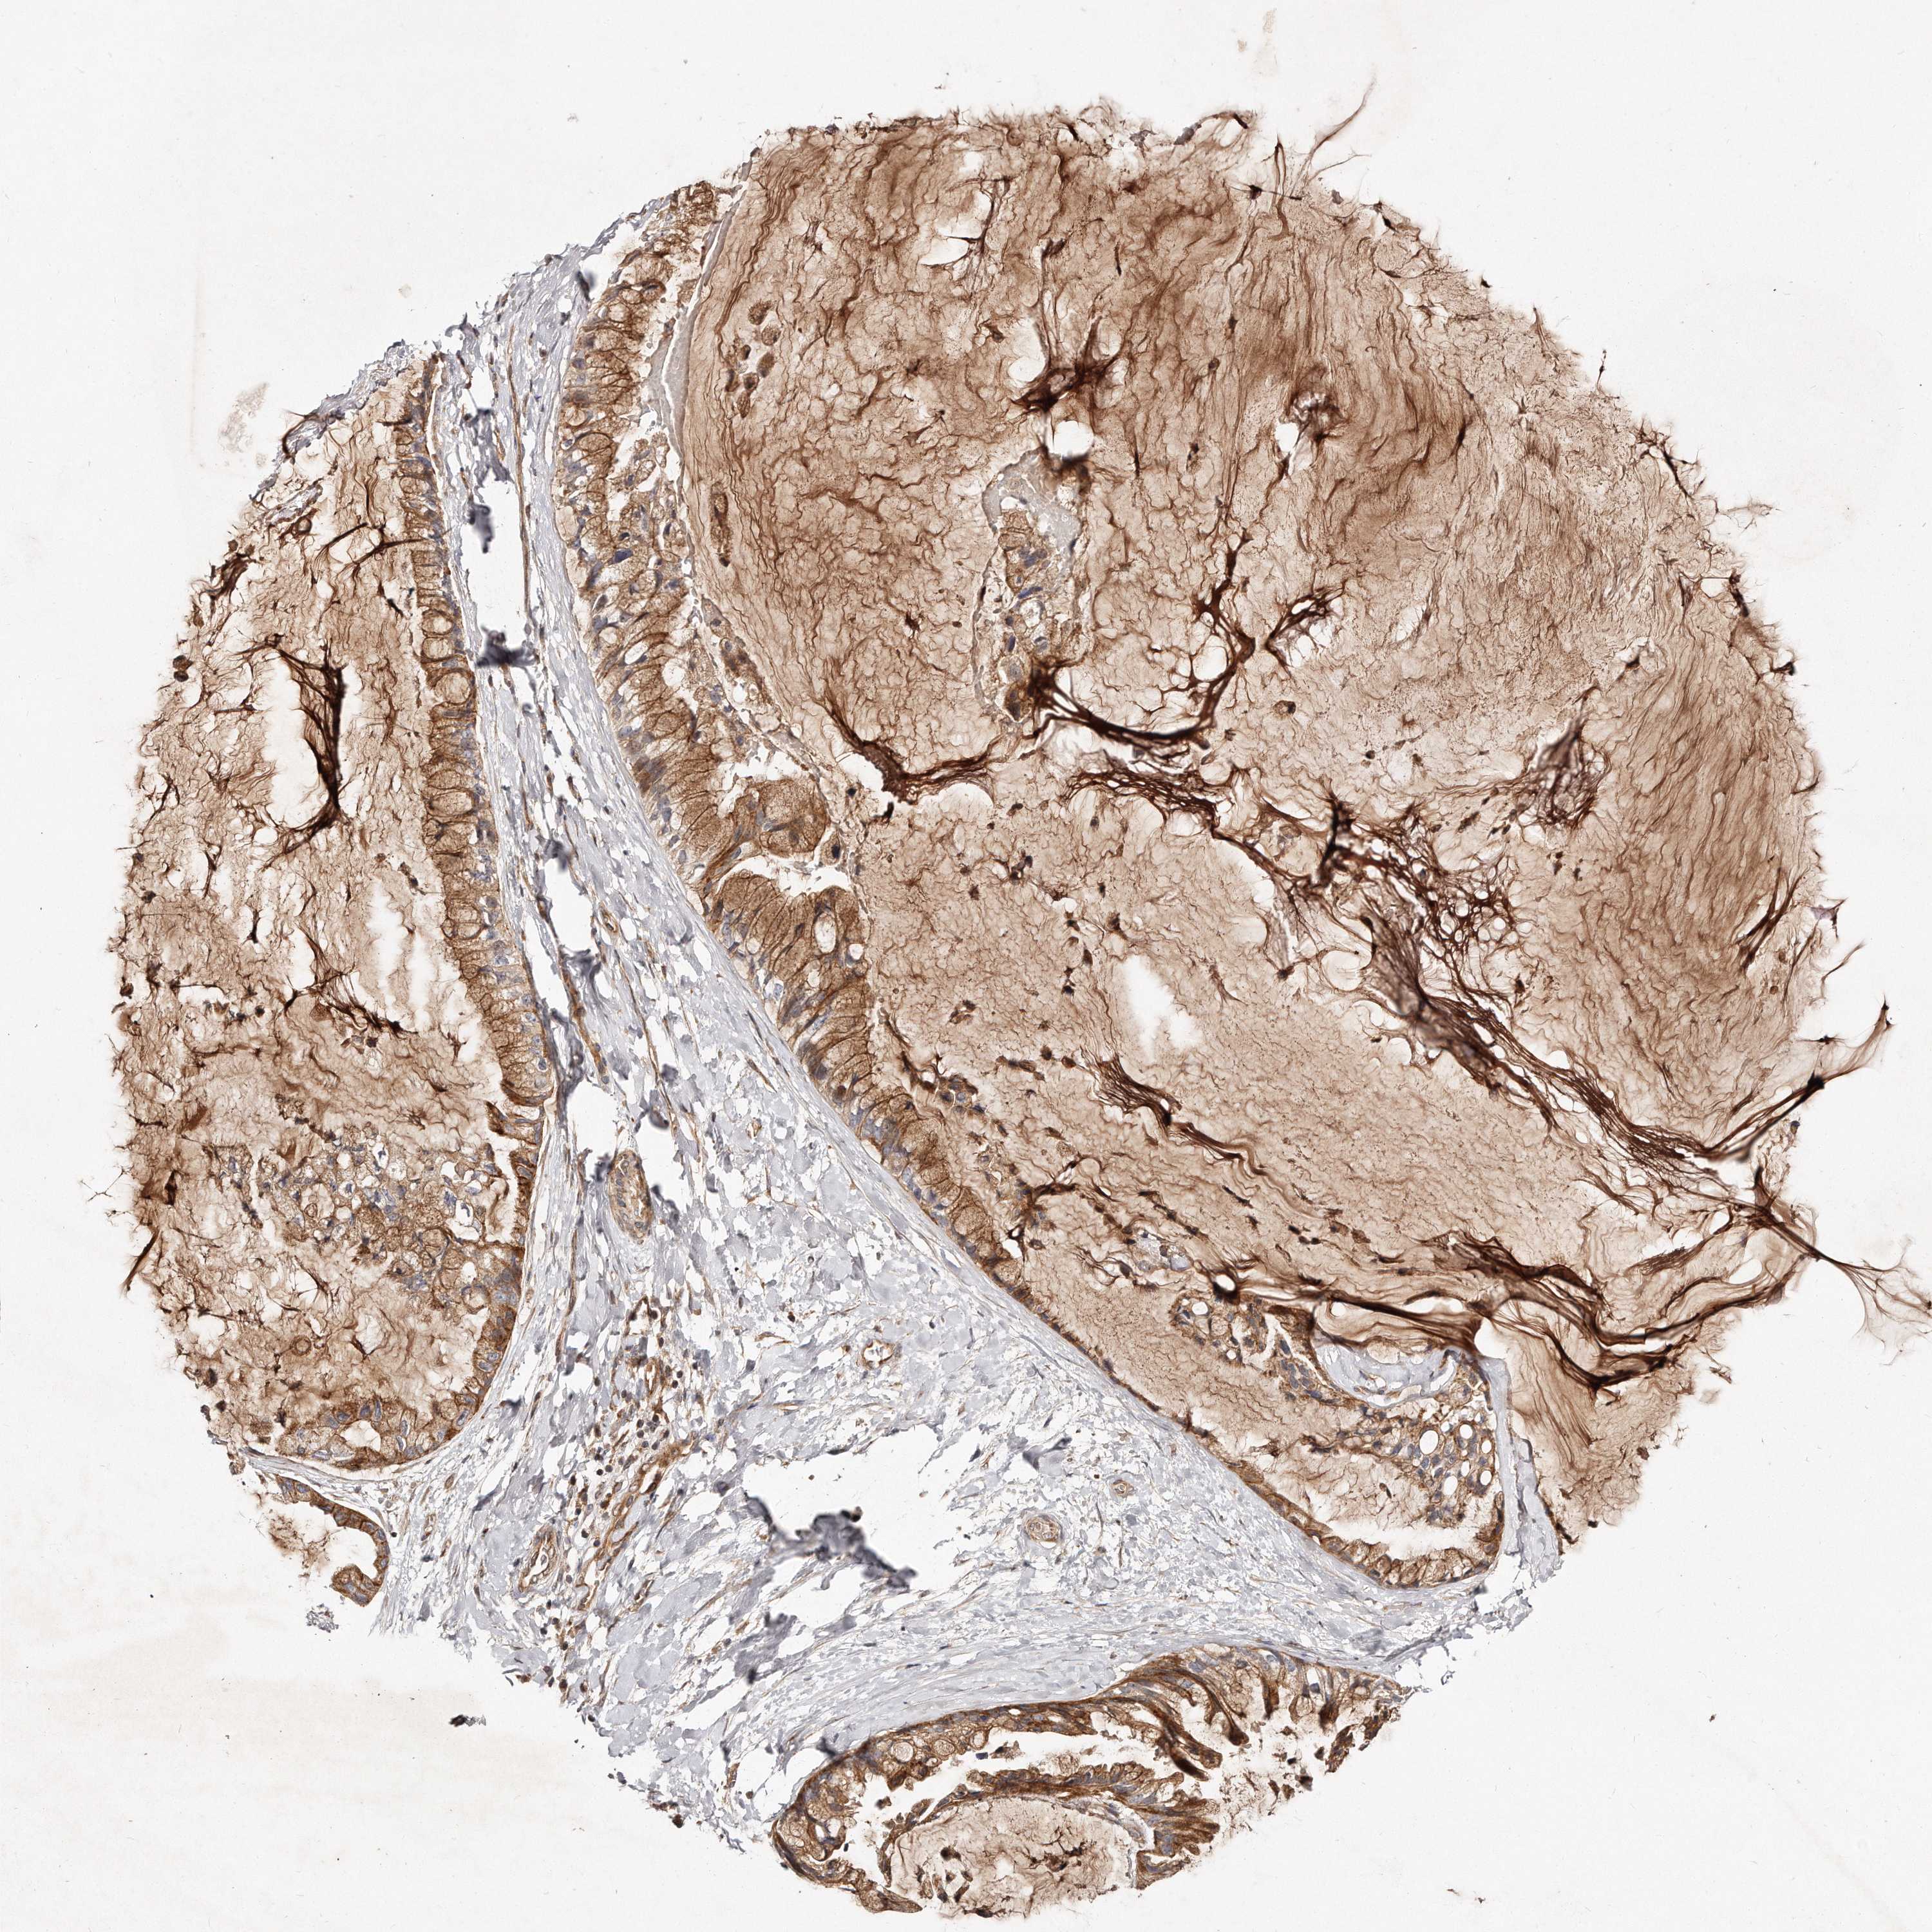

OVARIAN CANCER - Protein expressioni

A mouse-over function shows sample information and annotation data. Click on an image to view it in a full screen mode. Samples can be filtered based on level of antibody staining by selecting one or several of the following categories: high, medium, low and not detected. The assay and annotation is described here.

Note that samples used for immunohistochemistry by the Human Protein Atlas do not correspond to samples in the TCGA dataset.

Antibody stainingi

Antibody staining in the annotated cell types in the current human tissue is reported as not detected, low, medium, or high, based on conventional immunohistochemistry profiling in selected tissues. This score is based on the combination of the staining intensity and fraction of stained cells.

Each image is clickable and will lead to virtual microscopy that enables deeper exploration of all samples and also displays staining intensity scores, fraction scores and subcellular localization as well as patient and tissue information for each sample.

Antibody HPA030101

Staining

High

Medium

Low

Not detected

Intensity

Strong

Moderate

Weak

Negative

Quantity

>75%

75%-25%

<25%

None

Location

Nuclear

Cytoplasmic/membranous

Cytoplasmic/membranous,nuclear

Cystadenocarcinoma, serous, NOS

Carcinoma, endometroid

Cystadenocarcinoma, mucinous, NOS

Carcinoma, NOS